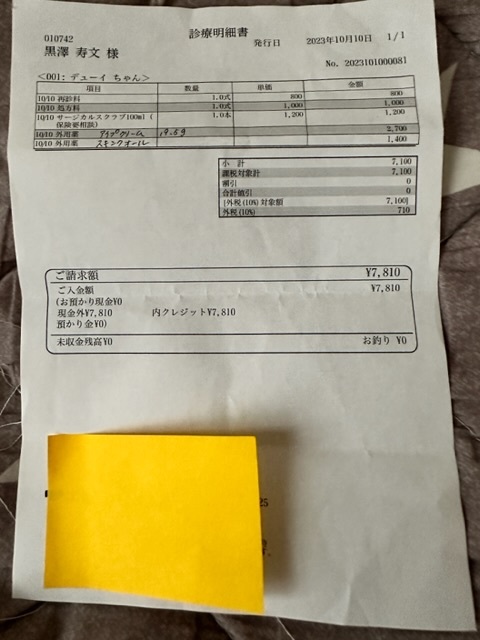

※上記は大学病院で頂いた診断書

※下記は初診かつ、会陰形成術をして頂く動物病院より発行して頂いた診断書、治療計画書

実際にかかった治療費

術後抜糸